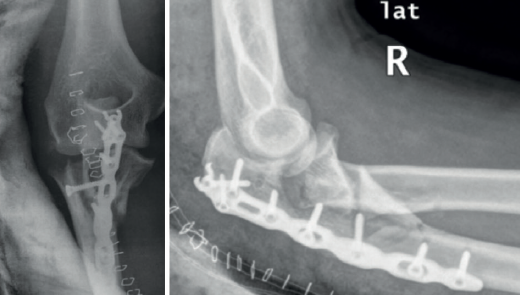

A pesar de que no existe un consenso en relación con la clasificación de las fracturas-luxaciones del codo y ateniéndonos al concepto fractura-luxación transolecraneana, en estas lesiones debe existir una fractura intraarticular del olécranon, con solución de continuidad en la cortical posterior del cúbito, en la que se ve comprometida la estabilidad humerocubital. Si no existe una luxación de la articulación radiocubital proximal, el término adecuado es “fractura-luxación transolecraneana” y, si se asocia una luxación de la articulación radiocubital proximal, “fractura-luxación variante de Monteggia” (Figura 1). Los estudios radiológicos no siempre permiten diferenciar claramente los patrones de fractura por lo que la tomografía axial computarizada (TAC) y especialmente las reconstrucciones tridimensionales son imprescindibles para su diagnóstico.

El desplazamiento del cúbito y del radio con respecto al húmero puede ser anterior o posterior tanto en la fractura-luxación transolecraneana como en la fractura-luxación variante de Monteggia (Figuras 2, 3 y 4). En los adultos, las fracturas-luxaciones transolecraneanas anteriores son menos frecuentes que las posteriores y se diferencian más fácilmente de las fracturas-luxaciones variante de Monteggia de tipo I que las fracturas-luxaciones transolecraneanas posteriores, que frecuentemente se confunden con fracturas-luxaciones variante de Monteggia de tipo II. En ambas lesiones existe una fractura intraarticular del olécranon, pueden asociar una fractura y/o luxación de la cabeza del radio y una fractura de la coronoides y, en las fracturas-luxaciones variante de Monteggia de tipo II, puede asociarse una lesión del ligamento colateral lateral(1,2,13,14,15).